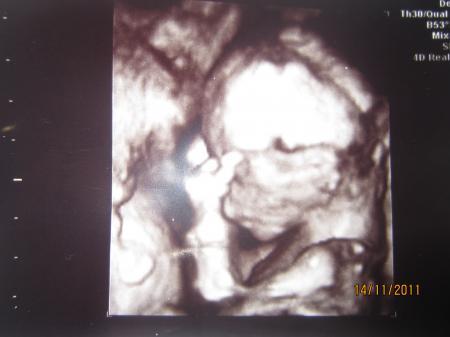

Foto Nr. 2 da sieht man das Baby von der Seite in 3D